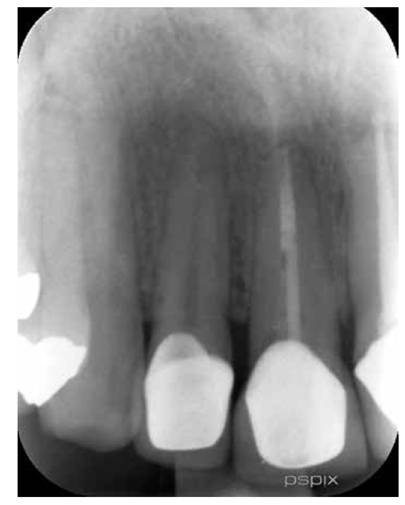

Paciente masculino de 36 años de edad sin antecedentes patológicos personales (A.P.P.) se presenta al Postgrado de Endodoncia de la Universidad Latina de Costa Rica por motivo de Trauma Dental debido un accidente laboral, el hecho ocurrió tres días anterior a su visita al centro de atención. Clínicamente se observa inflamación y un grado de movilidad II. Desalojo incisal y fuera de oclusión. (Figur 3) Radiográficamente se observa una obturación deficiente del conducto y a la vez una aparente fractura radicular. (Figura 4)

Figura 3: Inflamación de tejidos blandos y movilidad grado II de pieza 1.1, desalojamiento del alveolo y fuera de oclusión.

Figura 4: Radiografía inicial